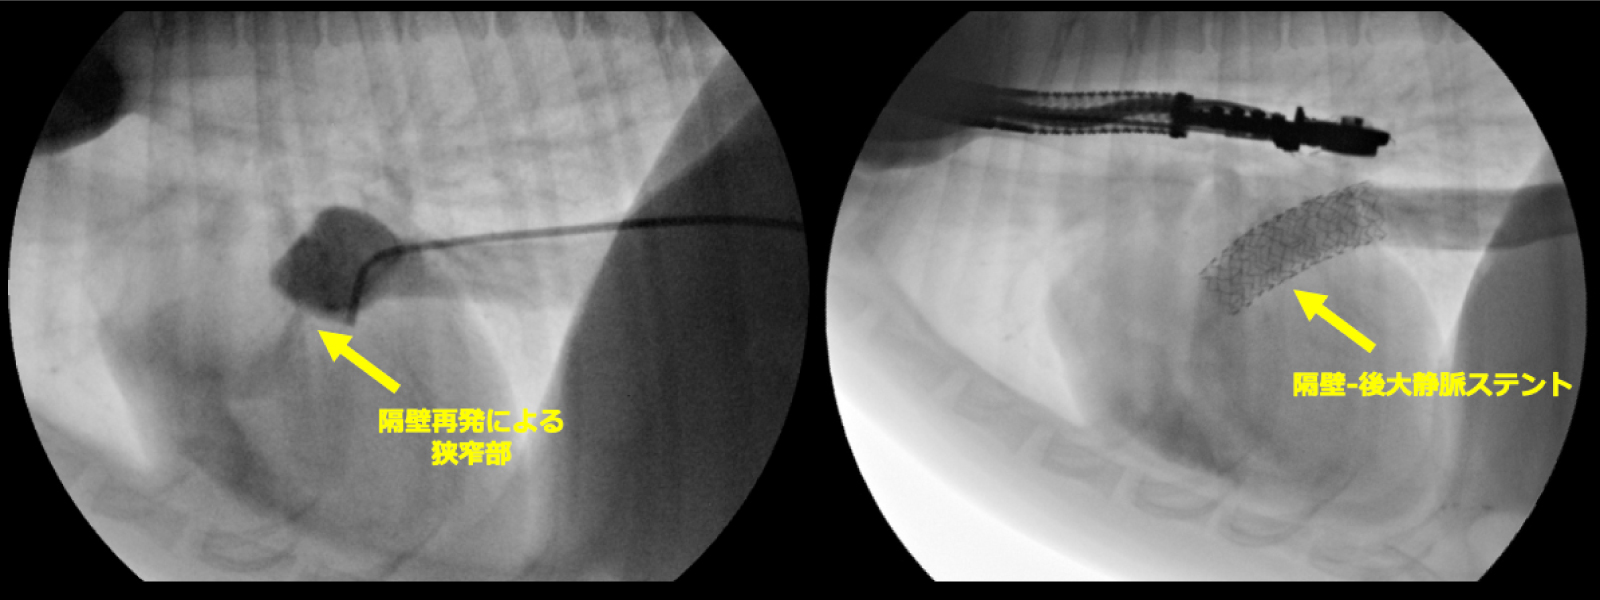

異常隔壁を全て除去することで隔壁孔を

4.3mm→9.0mmに拡張